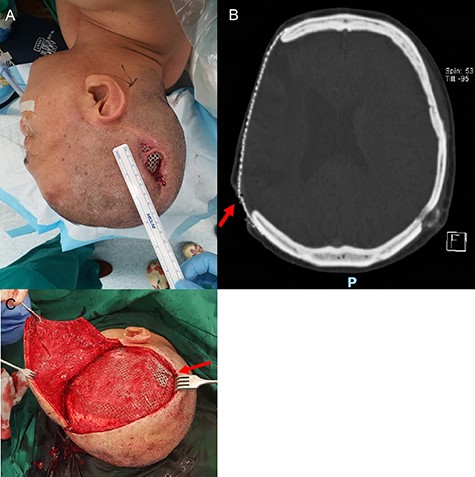

A 54-year-old man presented with a three-month history of a right parietal scalp wound, measuring 5 × 2.5 cm, with exposed titanium mesh (Fig. 1A). He had a post-traumatic decompressive craniectomy and titanium mesh cranioplasty 18 years ago. A computed tomography scan of the brain did not reveal any underlying collection and showed the configuration of the titanium mesh which resulted in the exposure (Fig. 1B). He was counselled for and underwent wound exploration, implant removal and exchange, and bipedicled flap reconstruction.

Parietal scalp wound with an exposed implant. A 54-year-old man presented with a right parietal scalp wound measuring 5 × 2.5 cm, with exposed titanium mesh cranioplasty implant (A). Computed tomography showed outward tenting of the implant beneath the area of exposure (B). This was correlated intraoperatively, due to venting cuts made from the initial surgery (C). This had likely caused pressure on the overlying skin and resulted in skin breakdown and implant exposure.